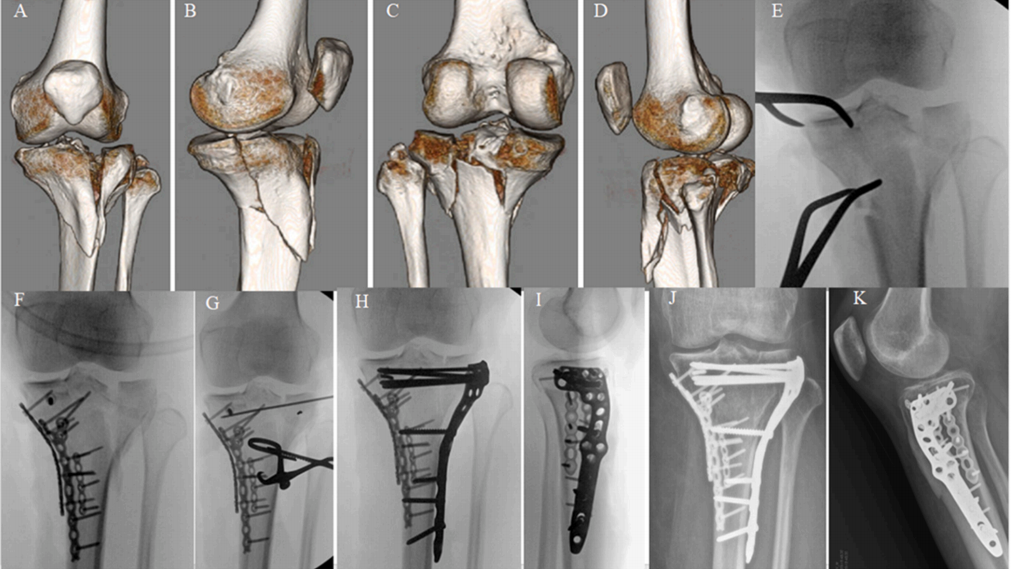

A-D) 55 岁男性多髁粉碎性胫骨平台骨折的 3D CT 图像。 E, F) 使用扩展后侧入路对后侧和内侧部分进行一期 ORIF 的术中 C 臂机图像。注意内侧边缘水平放置的钢板 G, H)。 I, J) 一期手术后 3 天,通过前外侧和内侧切口对前内侧和前外侧部分进行二期 ORIF 的术中 C 臂机图像。 I, J) 使用磷酸钙骨腻子(骨水泥)支撑前内侧缺损。二期 ORIF 术后即刻 X 光片。 K, L) 术后 34 周随访 X 光片显示骨折愈合且固定稳定性可接受。可注意到内侧胫骨平台轻度塌陷,但考虑到骨折特征,仍在可接受范围内。